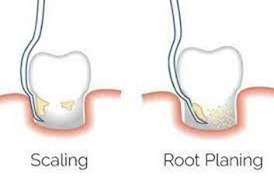

Will Deep Cleaning Stop Gum Disease? Sometimes, regular cleaning and polishing is not enough to prevent advanced gum diseases. In…

How Often Should You Get A Deep Teeth Cleaning? According to American dental association, dental check-ups and teeth cleaning should…